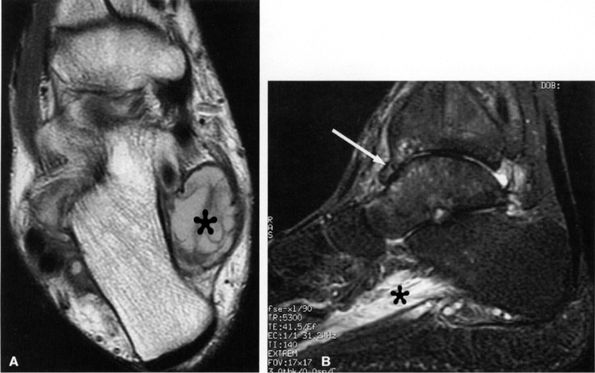

FIGURE 6.49 ● Tarsal tunnel syndrome and medial plantar nerve denervation edema due to proliferative synovitis. (A) Axial T2-weighted image demonstrates a synovial mass (asterisk) in the tarsal tunnel. (B) Sagittal T2-weighted fat-suppressed image illustrates denervation edema in the flexor digitorum brevis muscle (asterisk). Note associated osteoarthritic changes in the anterior tibiotalar joint (arrow).

|

Muscle denervation edema or atrophy of the abductor hallucis and flexor digitorum brevis muscles, seen on MR images of the ankle, is compatible with medial plantar nerve entrapment (Fig. 6.52).

-

Denervation of the first lumbrical and of the flexor hallucis brevis muscle, also consistent with medial plantar nerve entrapment, is better seen on MR images of the foot (Figs. 6.53 and 6.54).